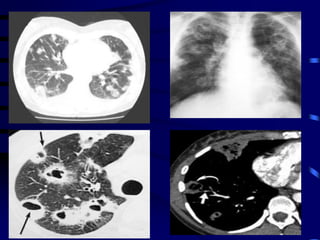

The patient was initially treated for

severe pneumonia and a chest

radiography followed by computed

(CT) scan of the chest were obtained .

On the basis of radiological findings, what

is your diagnosis ?

1-Septic pulmonary

embolism.

2- Cavitating pneumonia.

3- Pulmonary TB

4-Cavitating secondaries

On the basis of the CT findings, the

diagnosis of infected pulmonary

emboli was considered and right-

sided infective endocarditis (IE) was

suspected. This was supported by

positive blood culture result. However,

the transthoracic echocardiogram

(TTE) showed no vegetations.